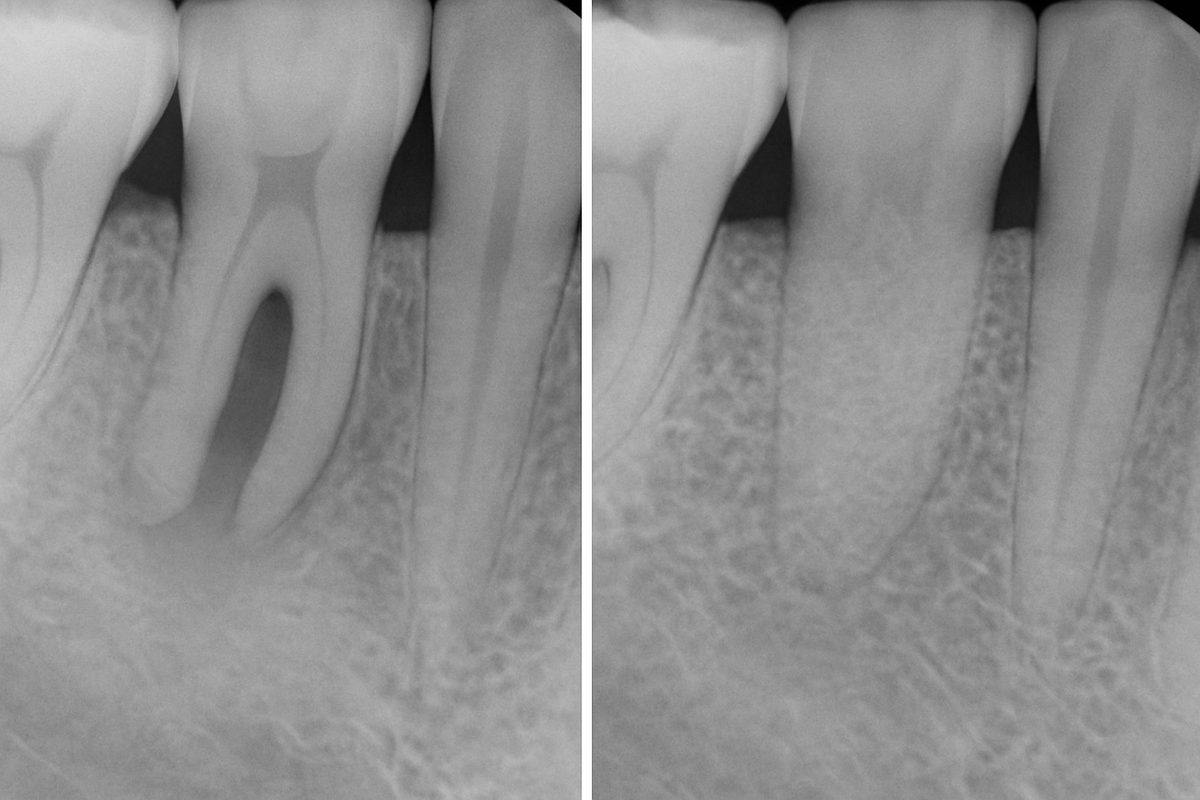

Dental implant grafting in Minneapolis is commonly needed after tooth loss leads to bone shrinkage. Other reasons include infection after an extraction, trauma, long‑term missing teeth, ridge defects, or changes in the sinus that reduce upper jaw bone height.

Grafting can be immediate (at the time of extraction) or delayed. Socket preservation after extraction reduces future bone loss and can simplify later implant placement. Your dentist will recommend timing based on your anatomy and goals.